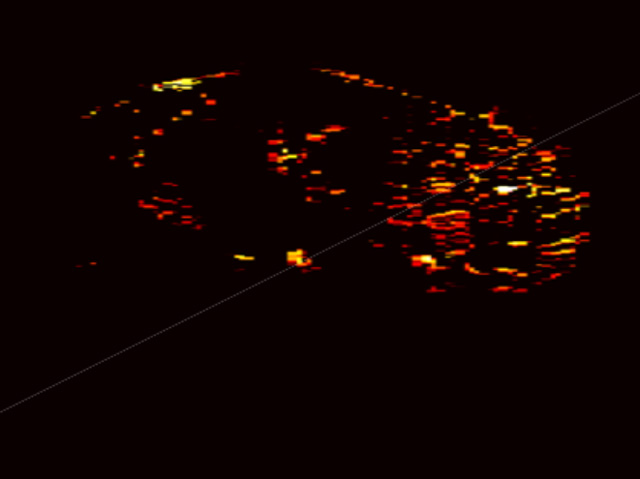

Photoacoustic maps of the degree of scarring within the kidney. The color intensity denotes the concentration of collagen, the core component of kidney scarring.

Each kind of body tissue absorbs coloured laser light in its own unique way. Collagen – one of the main components in kidney scarring – absorbs colour in a manner that is distinct from other components in the kidney. Spectral unmixing teases out the differences. Maps generated by the technology show the amount and distribution of collagen, blood or other tissue – thus allowing physicians to ‘see’ the quality of donated kidneys.

In less than two minutes, the new technique can generate a 2D image with enough detail to quantify total scarring in a kidney. Within 15 minutes, 3D imaging allows visualization not only of overall scarring, but also its varied distribution throughout the kidney.